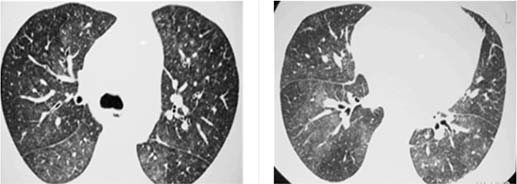

Um Paciente de 25 anos de idade, com tosse e febre de início súbitos 60 dias após transplante de medula óssea, realizou RT-PCR para Covid-19, cujo resultado foi negativo. Constataram-se exame de BAAR negativo, teste de Mantoux negativo e fibrobroncoscopia com cultura e BAAR negativos. A tomografia de tórax apresenta opacidades com atenuação em vidro fosco e pequenos nódulos pulmonares bilaterais, conforme as imagens a seguir.

Considerando esse caso clínico, as imagens apresentadas e os conhecimentos médicos correlatos, julgue os itens a seguir.